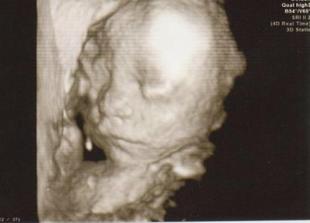

Náš anjelik